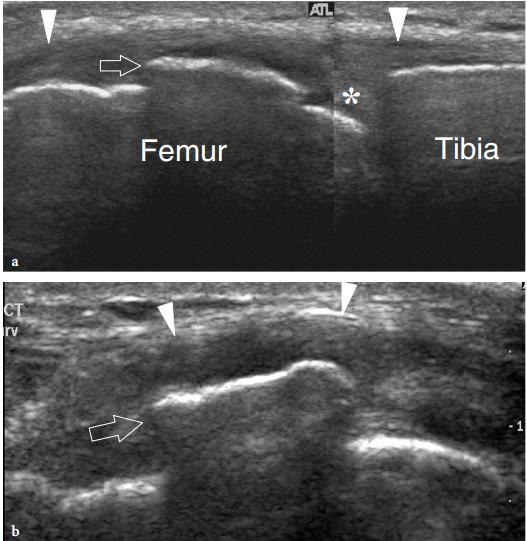

鹅足滑囊痛综合征(PAPS):既往称为鹅足滑囊炎(anserine bursitis)。但新近的骨骼肌肉超声、病理解剖证实,我们很少能看到滑囊的炎症性改变。因此诊断滑囊痛综合征更为合适。该病变最常见于糖尿病患者。像女性、肥胖、骨关节炎病人都相对易发生。主要症状特征是:内侧膝关节痛、上胫骨压痛;且没有局部肿胀、硬结等。

如存在鹅足滑囊的肿胀、局部温度增高等,这应诊断鹅足滑囊炎。鹅足滑囊炎更见于痛风、CPPD、感染。然而,真正的鹅足滑囊炎是很少见的。

实心剪头所指肌腱附着处增厚。空心三角指内侧副韧带处少量积液